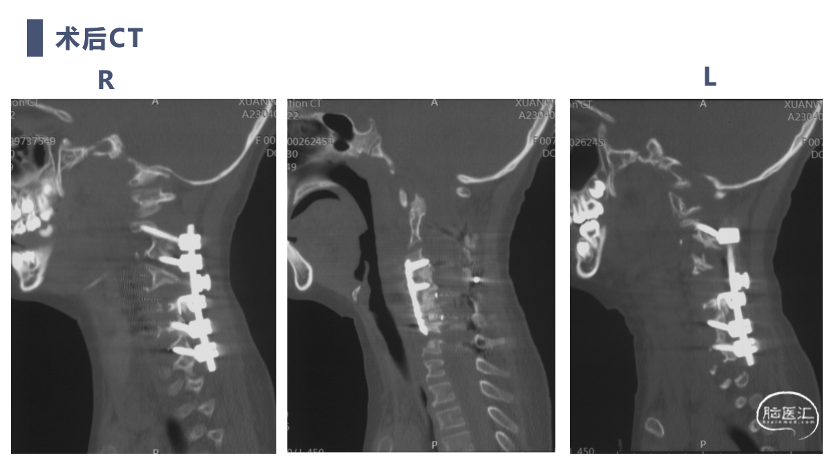

术后CT

CT显示颈椎椎体最大深度只有8mm,枢椎椎弓根直径3.2mm

双向牵引后,患者后方小关节仍存在一定绞锁,首先行后路手术,充分松解后方绞锁的关节突。再行前路手术,矫正后凸畸形,前路手术时因患者骨量极少,单纯前路螺钉复位力量弱,借助提拉工具完成良好复位。最后翻身行后路手术完成C2-7后路固定,因患者多数侧块发育异常,双侧C4-5无法置钉,应用椎板钩固定,双侧C2椎弓根直径只有3.2mm,但成功置入了两颗3.5mm螺钉。

术后复查患者复位满意,颈痛及神经症状消失,但此类患儿骨性结构发育异常,需要密切随诊,观察有无近端或远端交界性后凸发生。